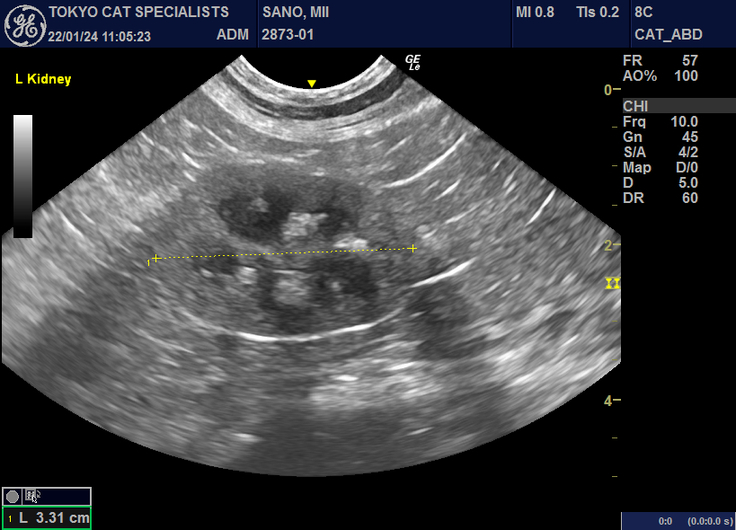

※リンパ腫の確定診断

(病院に掲載許可を頂きました)

※病院に掲載許可を頂きました。

▼プロジェクト終了要項 ●治療対象 みーちゃん(猫、MIX、15歳、メス) ●治療内容 みーちゃんの悪性リンパ腫を抗がん剤治療で寛解させたい。 小腸付近の消化器型リンパ腫への抗がん剤や投薬による治療とともに転移した眼の奥、頭蓋内リンパ腫による失明への抗がん剤や投薬による治療。血液検査とエコー検査などの各種検査をさせていただきたいです。助けてください。 ●治療完了予定日 2023/3/1